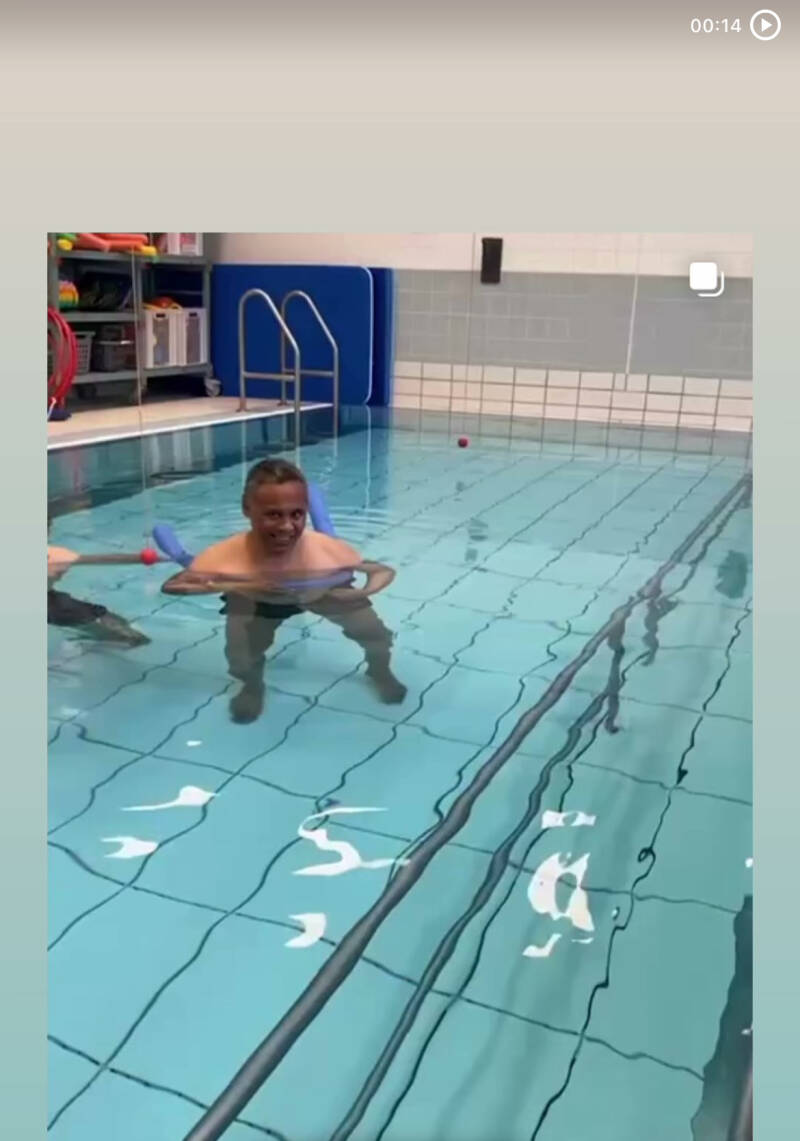

eerstekeerzwemles

Na mijn herseninfarct heb ik staand badminton en het zwemmen herontdekt. Ook fiets ik weer regelmatig. Deze sporten geven mij energie en helpen mij om fit te blijven. Het is geweldig om te ervaren dat ik nog steeds actief kan zijn en plezier kan hebben in sport, ondanks mijn beperkingen.